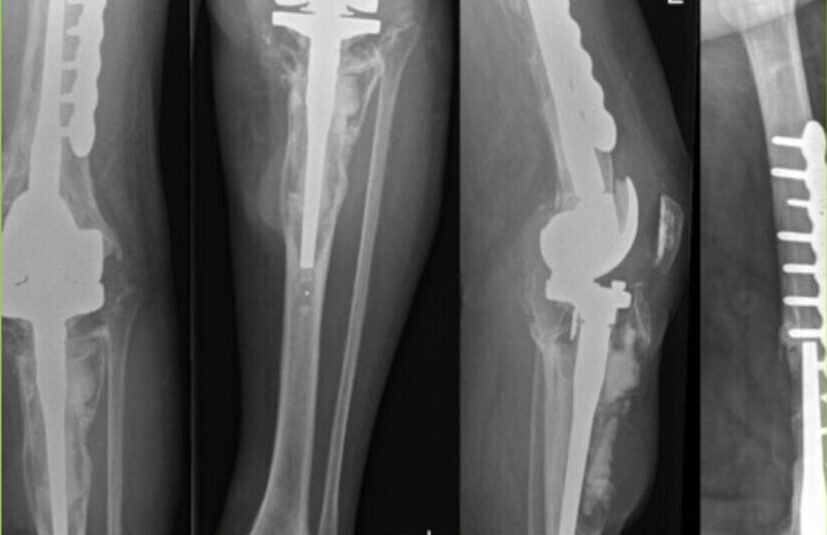

Revision Knee Replacement is a surgical procedure performed when a previously replaced knee joint has developed complications, such as aseptic loosening or infection. Aseptic loosening occurs when the artificial components of the knee joint become loose due to factors such as wear and tear, implant failure, or bone loss. Infection can occur when bacteria enter the knee joint, leading to pain, swelling, and limited mobility. Revision Knee Replacement involves removing the existing components and replacing them with new ones to restore knee function and alleviate pain.

2. Revision Knee Replacement Surgery: Our skilled surgeons perform revision knee replacement surgeries using advanced techniques and state-of-the-art facilities. The procedure involves removing the existing components, thoroughly cleaning the joint to address infection, addressing bone loss if present, and replacing the components with new implants to restore knee function and stability.